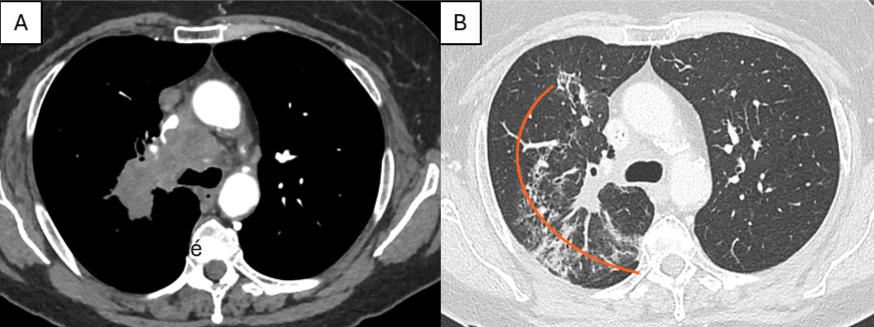

La radiologie interventionnelle redéfinit la prise en charge des traumatismes chez les sportifs de haut niveau. Des nouvelles procédures offrent des solutions thérapeutiques qui réduisent la morbidité, épargnent les tissus mous et autorisent un retour à l’entraînement ...